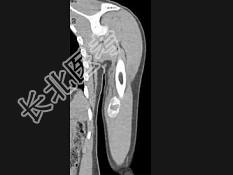

- 单项选择题男,21岁, 左上肢有外伤史,现感局部疼痛, 可扪及包块,结合图像, 最可能的诊断是 ( )

A、骨外骨肉瘤

B、骨外软骨肉瘤

C、皮质旁骨肉瘤

D、邻皮质软骨瘤

E、骨化性肌炎